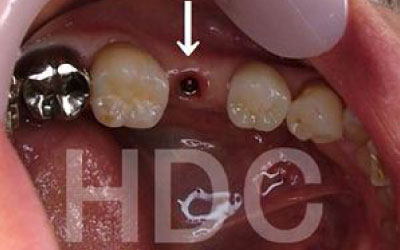

一方、インプラントは人工の歯根が顎の骨に直接固定されるため、残っている歯にかかる負担を大幅に軽減できます。

一方でインプラント治療なら、周囲の歯を削ったり神経を抜いたりする必要がないため、健康な歯を守りながら歯の寿命を延ばすことができます。

インプラントの利点は、入れ歯のように取り外す必要がなく、ご自身の歯のように自然に噛める点です。

そして最大の利点は、周囲の歯の寿命を短くしないことです。

ブリッジや入れ歯では、他の歯に負担がかかり、歯が連鎖的に抜けていくことがあります。

しかし、インプラントは周囲の歯に一切負担をかけないため、残った歯にとって最も優しい治療法です。